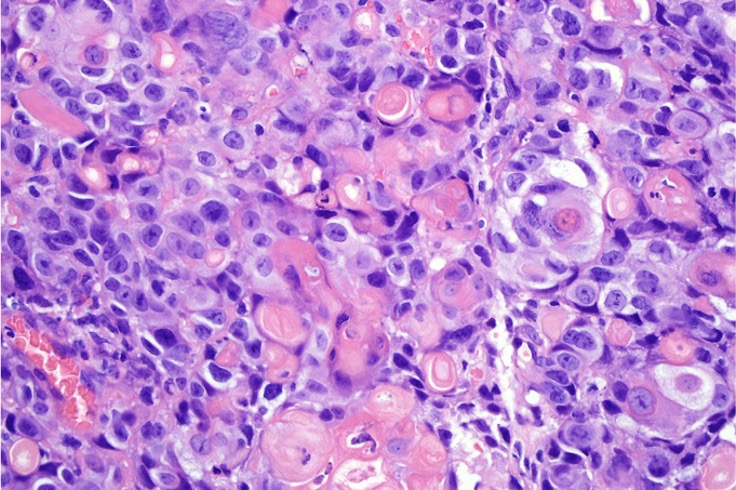

•Basaloid population with prominent nucleoli accompanied by supramatricial and ghost cells

•Variable pleomorphism

•Mitoses may be conspicuous

•Heavily pigmented dendritic +/- epithelioid melanocytes